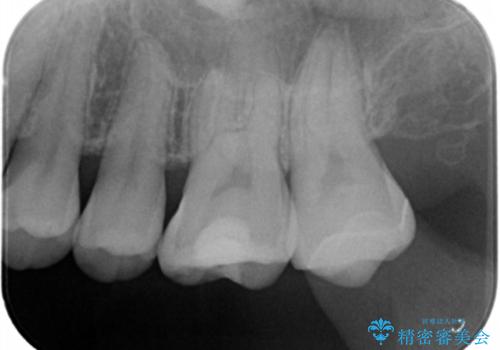

拡大鏡下で古いプラスチックを除去して虫歯がないことを確認して

e-maxインレーにて治療しました。

白い詰め物が入り、ザラザラもなくなりました。

一つ手前の古いプラスチックで治療されている歯も現在詰め物にやりかえを検討中です。